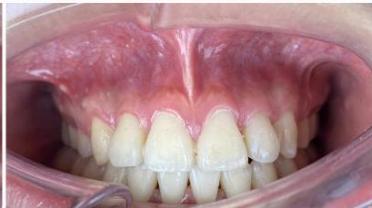

## IX. TREATMENT RESULTS

After appliance removal, bilateral Class I canine and first molar relationships were achieved, with stable intercuspation. The maxillary and mandibular dental midlines were coincident, and both overjet and overbite were approximately $2\mathrm{mm}$. The dental arches in both jaws were well aligned, leveled, and exhibited a standardized arch form.

With respect to soft tissue outcomes, facial esthetics improved markedly, transitioning from a convex facial profile with lip protrusion relative to the E-line to a more harmonious facial profile with an E-line position approaching physiological norms. Mentalis muscle strain was reduced, facial esthetics were significantly enhanced, and the patient expressed satisfaction with the treatment outcome.

Notably, the mandibular incisor roots did not perforate the labial cortical plate and did not exhibit a clinically significant increase in negative torque, despite the prolonged space closure phase. This finding is of particular clinical relevance given the unfavorable biological limitations present at the beginning of treatment.

Figure 10: Post-treatment intraoral photographs